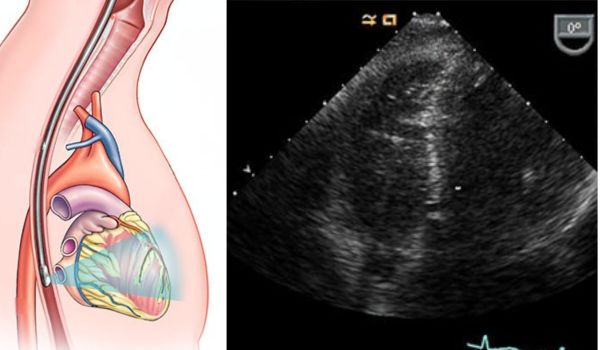

Трансезофагеальна ехокардіографія